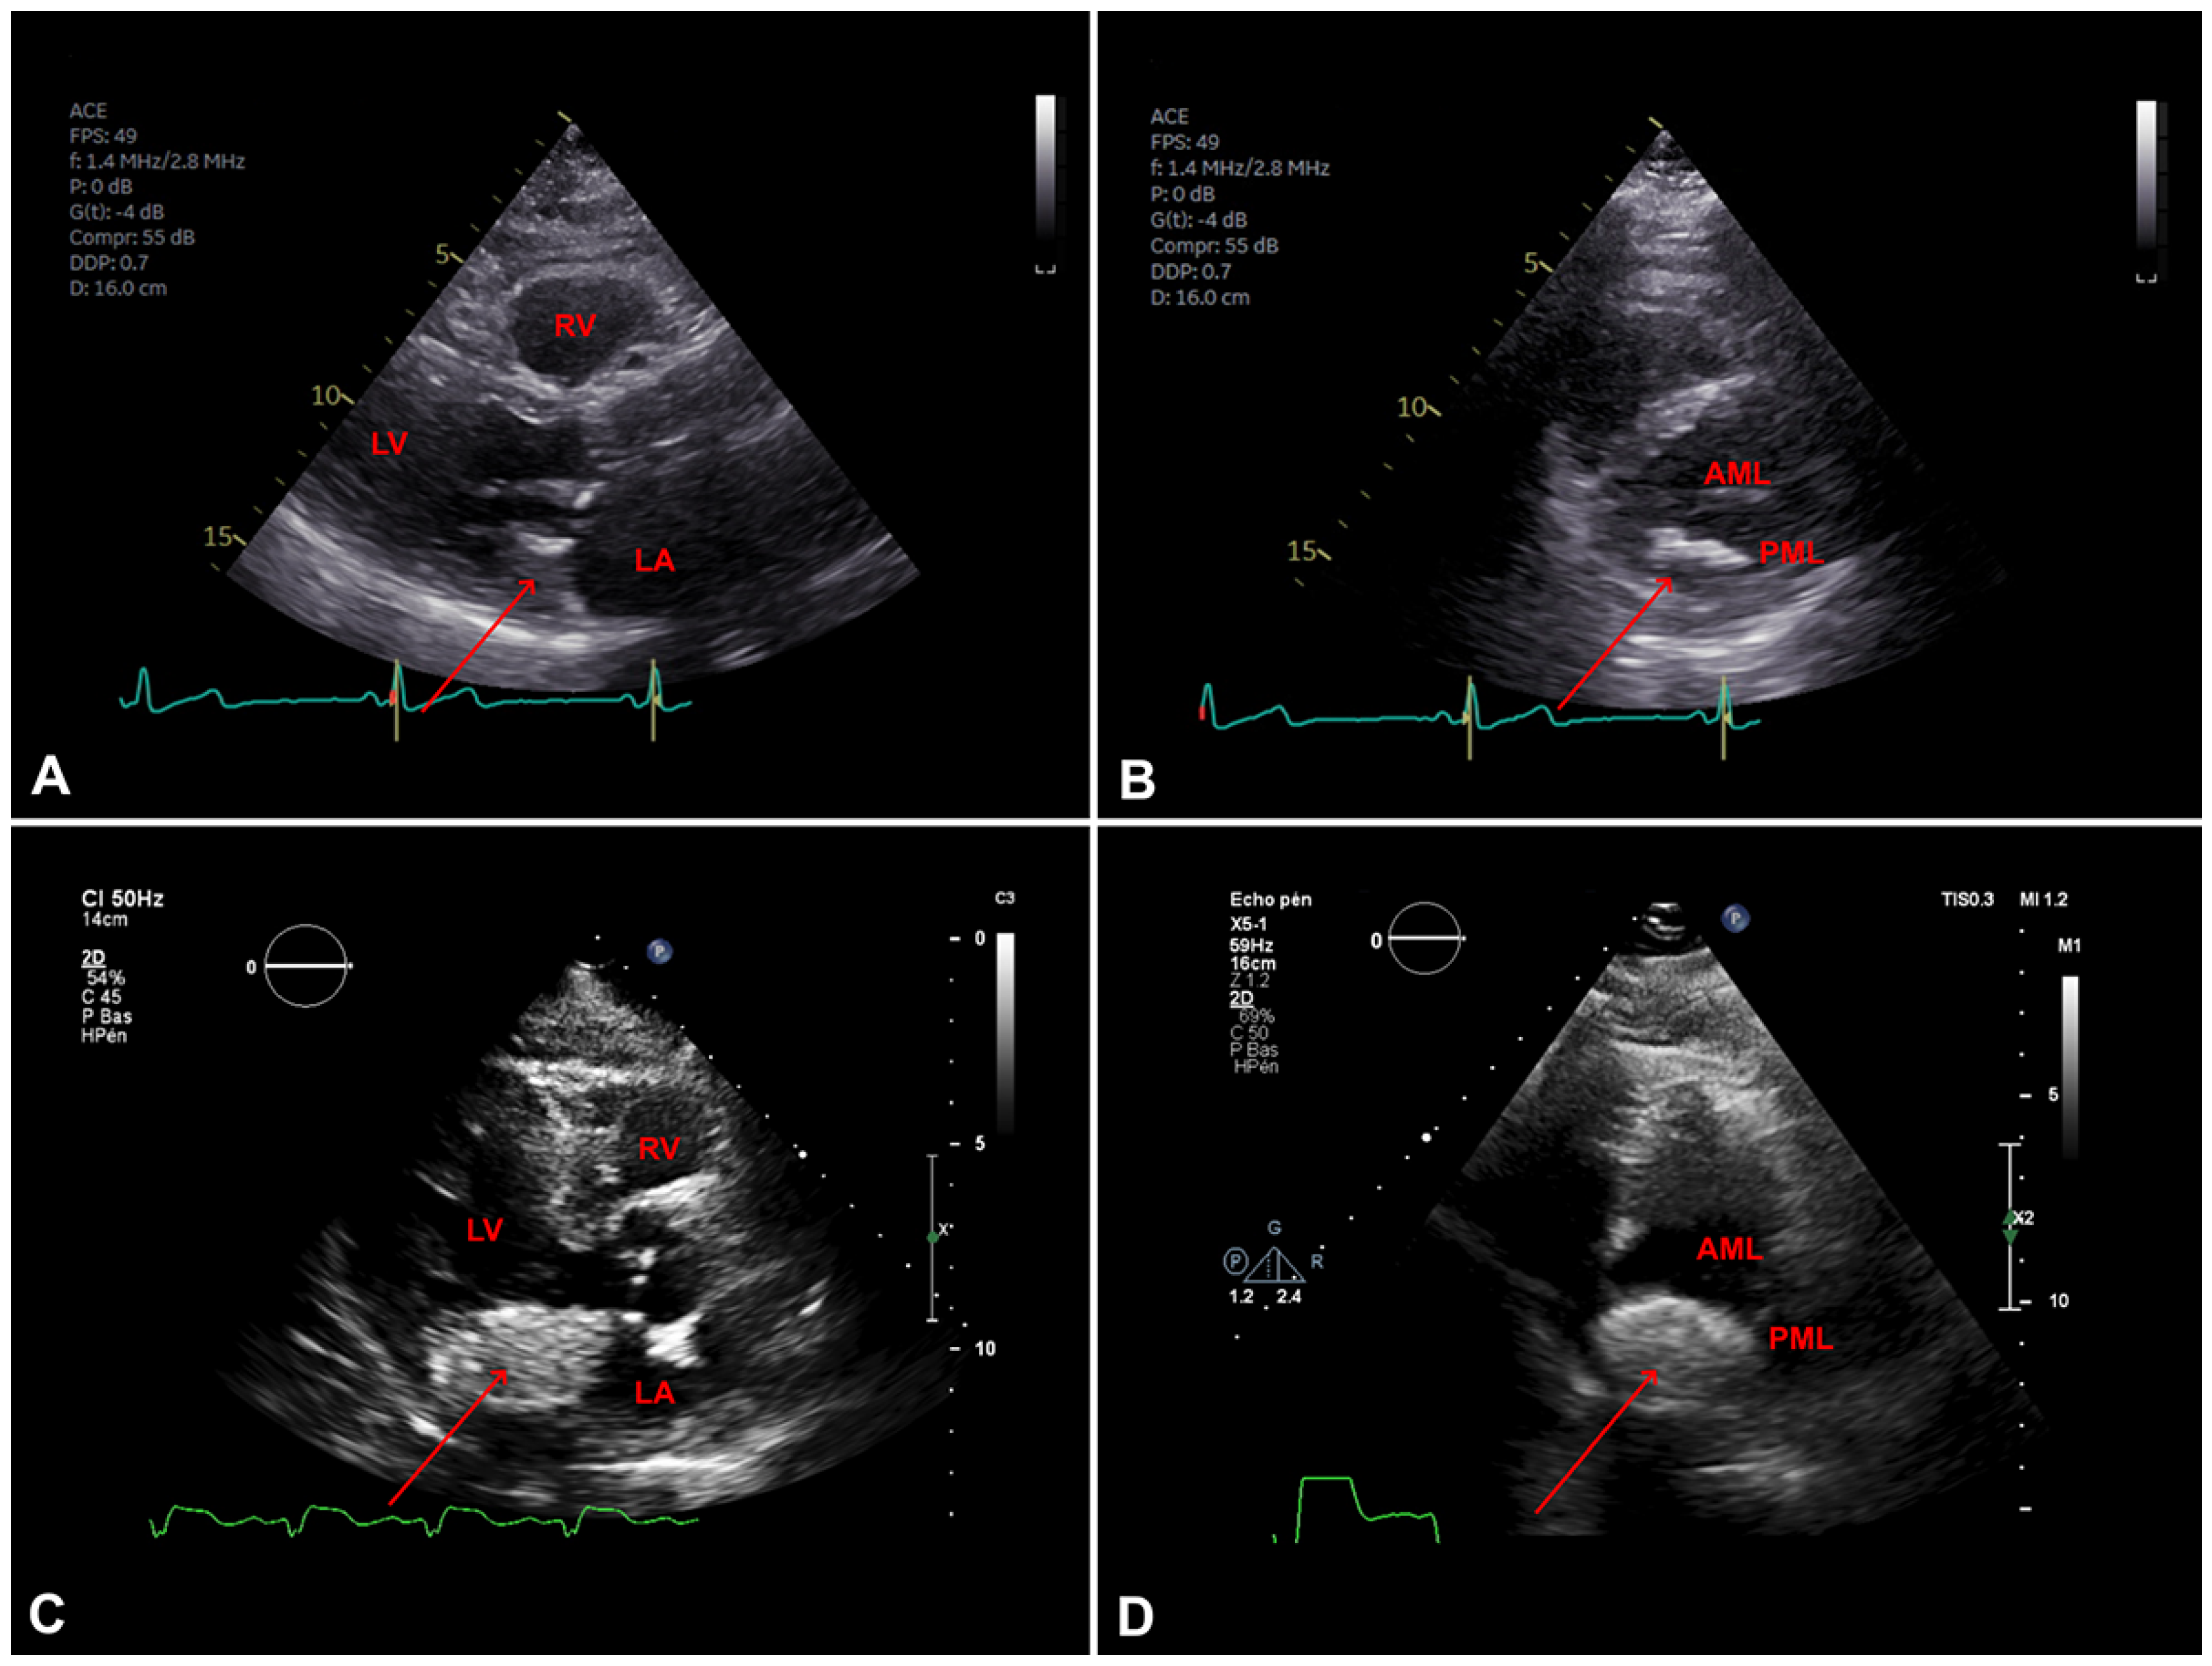

Figure 6. A. Transothoracic echocardiography (TTE) parasternal long axis view showing mitral annular calcification (MAC) (arrow), LV: left ventricle; LA: left atrium; RV: right ventricule. B. TTE parasternal short axis view showing mitral valve with MAC (arrow), PML: posterior mitral leaflet; AML: anterior mitral leaflet. C. TTE parasternal long axis view showing (arrow), LV:left ventricle LA: left atrium;RV: right ventricule. D. TTE parasternal short axis view showing mitral valve with caseous calcification (arrow), PML: posterior mitral leaflet; AML: anterior mitral leaflet.

On transthoracic echocardiography (TEE), appears as a round calcification, with well-defined brightened edges corresponding to an echodense periphery, and a central echolucent area corresponding to the central liquefaction area. Colour Doppler shows a lack of flow inside the central zone [1,7]. Differences between mitral annular calcification and caseous calcification on TEE are summarised on Table 2 and illustrated in Figure 6.